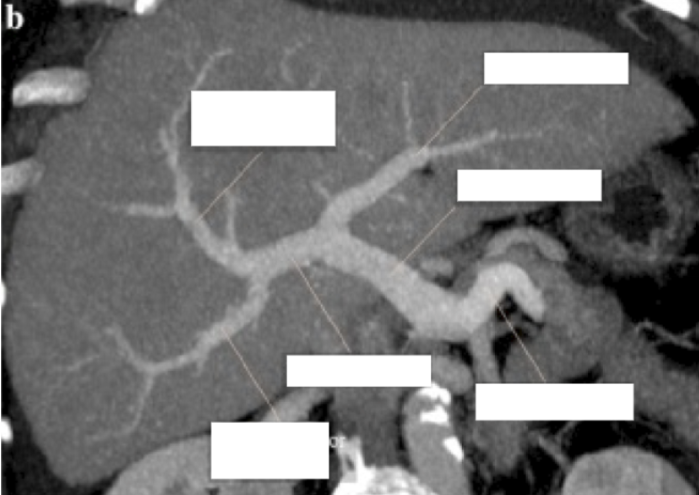

Label the CT abdomen

right hemidiaphragm

segment VIII of the liver

inferior vena cava

Please label 5 and 6

left hepatic vein

right hepatic vein

Please label 9

Gatstric fundus

10 and 11 are segments of the liver. Label which segments they are

segment II of the liver

segment IV of the liver

Please label 18 and 19

Segment III of the liver

Left Hepatic artery

20 and 21 are both blood vessels. Label which blood vessels they are

right portal vein

right splenic artery

Label 23 and 24

Segment V of the liver

Splenic vein

Label 25 and 26

Common hepatic duct

Segment VI of the liver

What is 27 and 28?

Splenic flexure

Left gastric artery

What is 38 and 40?

Falciform ligament

neck of the gallbladder

Label 41 and 42

main pancreatic duct

body of gallbladder

Please label 55 - 58

left portal vein

common bile duct

uncinate process of the pancreas